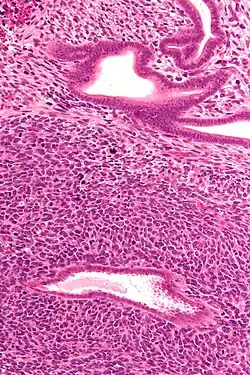

Micrograph of a uterine adenosarcoma showing a mitotically active malignant stroma and benign glands. H&E stain.

Uterine adenosarcoma have, by definition, a malignant stroma and benign glandular elements. The World Health Organization (WHO) criteria have a mitotic rate cut point; however, this is often disregarded, as bland-appearing tumours with a low mitotic rate are known to metastasize occasionally.[2]